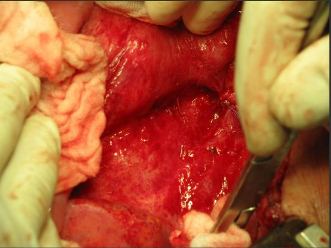

Operačná liečba

- Laparotomickým prístupom

- Laparoskopickým prístupom

- Verifikovať miesto úniku lymfy lymfografiou – Patent blue

- Sutúra

Sachs P.B.: AJR 1991, 157, 703-705